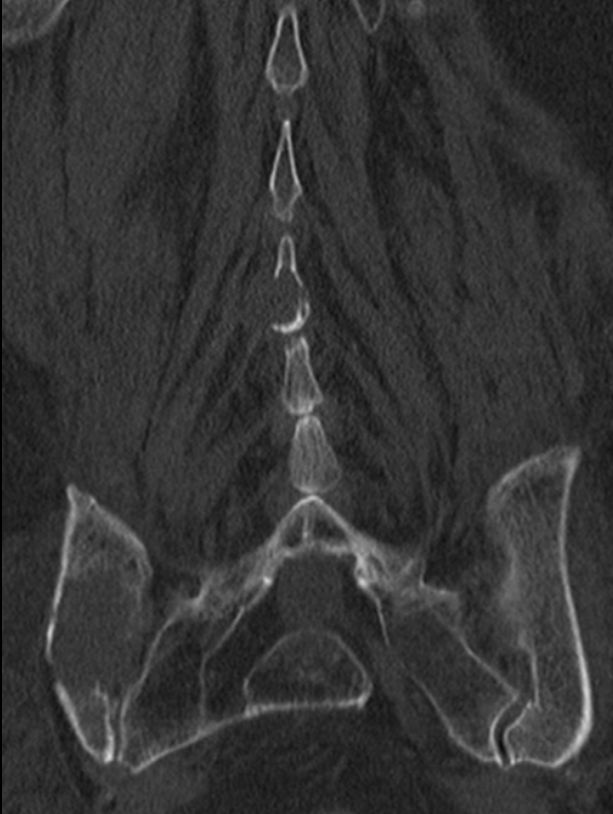

8 Monate nach Primärtherapie auftreten von Knochenmetastasen. Kein lokales Rezidiv.